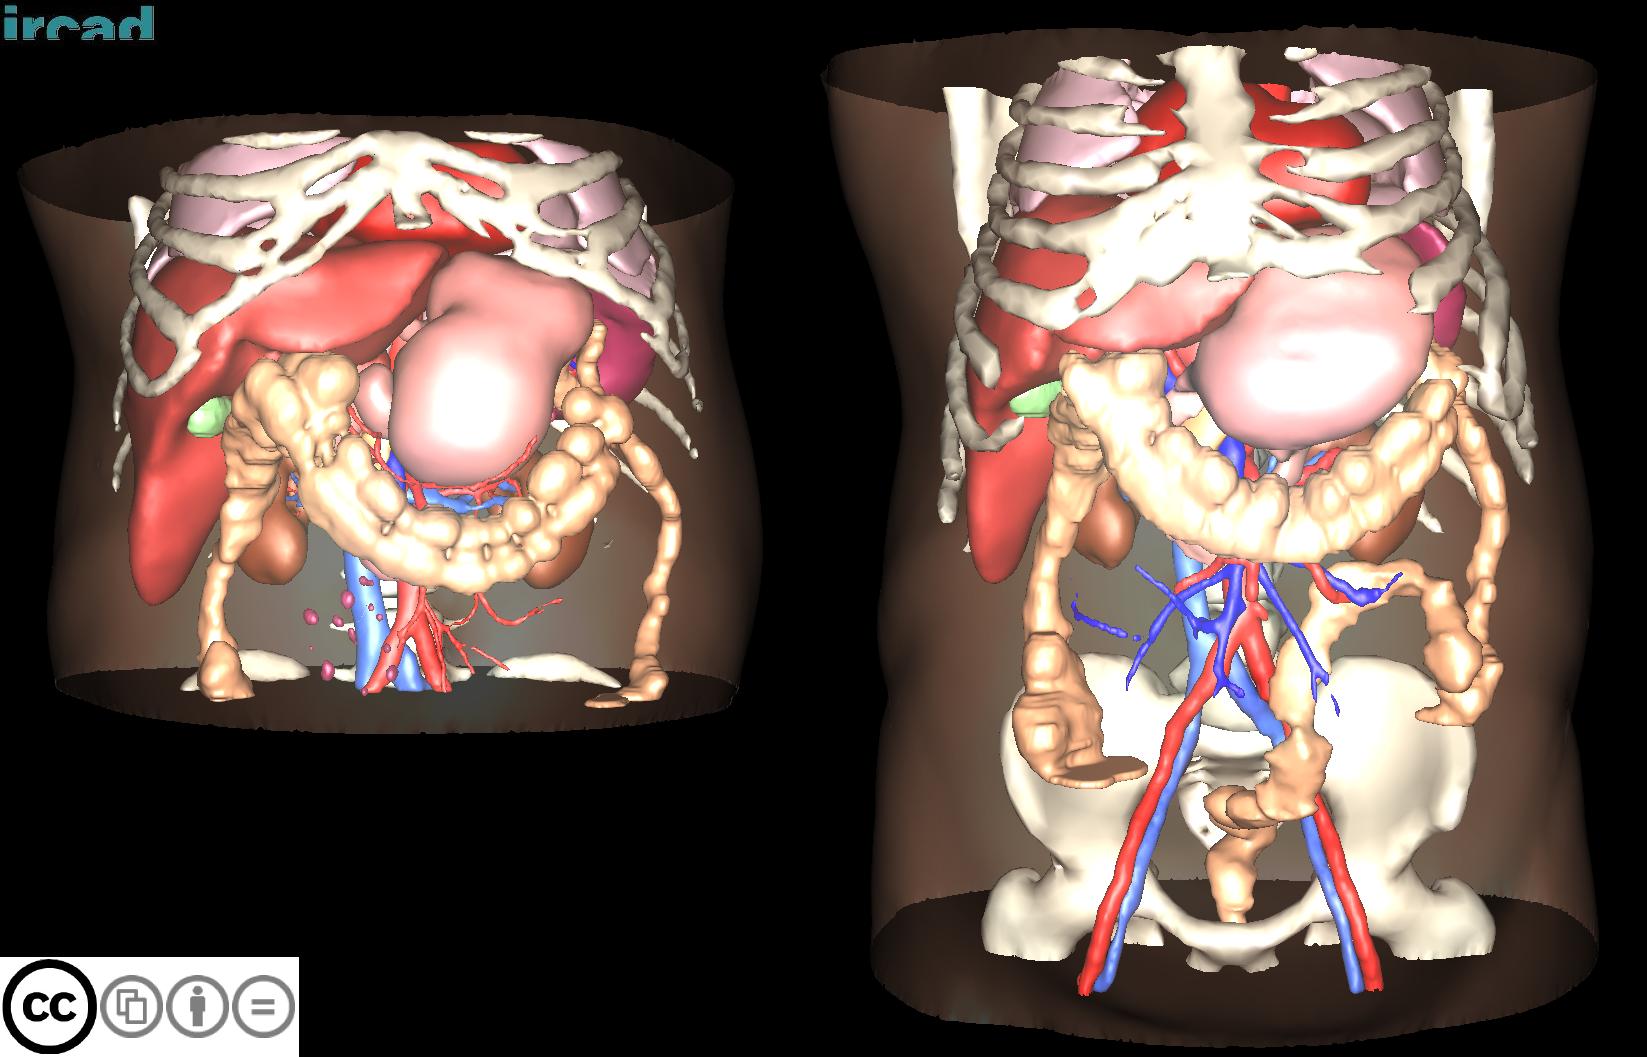

3D-IRCADB

| 3D-IRCADb 01 02 | 肝脏/肝肿瘤 | 分割 | CT | 20+2 | surface mesh | dcm | CC |

3D-IRCADb是比较早的一个数据集,有两个子集,分别包含20组和2组CT片子。

CHAOS

| CHAOS | 肝/肾/脾 | 分割 | CT+MRI | 40CT+120MRI | 0/1标签 | dcm | CC 4.0 |

CHAOS是一个多脏器,多模态分割数据集。